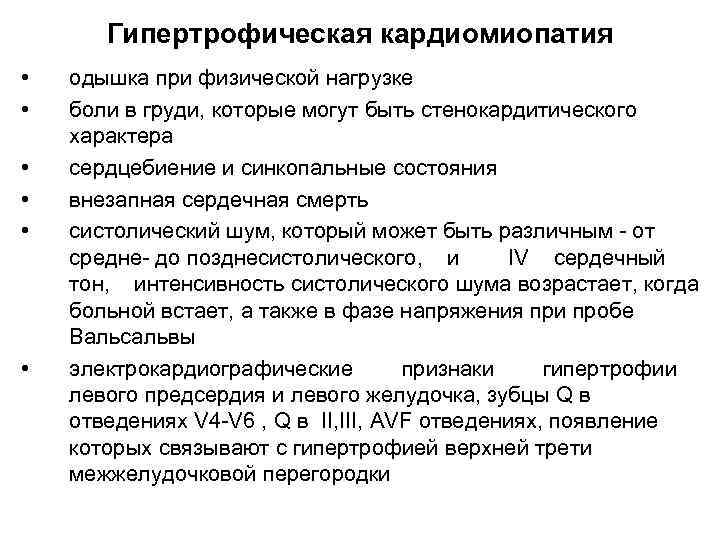

Гипертрофическая кардиомиопатия • • • одышка при физической нагрузке боли в груди, которые могут быть стенокардитического характера сердцебиение и синкопальные состояния внезапная сердечная смерть систолический шум, который может быть различным - от средне- до позднесистолического, и IV сердечный тон, интенсивность систолического шума возрастает, когда больной встает, а также в фазе напряжения при пробе Вальсальвы электрокардиографические признаки гипертрофии левого предсердия и левого желудочка, зубцы Q в отведениях V 4 -V 6 , Q в II, III, AVF отведениях, появление которых связывают с гипертрофией верхней трети межжелудочковой перегородки

Гипертрофическая кардиомиопатия • • • одышка при физической нагрузке боли в груди, которые могут быть стенокардитического характера сердцебиение и синкопальные состояния внезапная сердечная смерть систолический шум, который может быть различным - от средне- до позднесистолического, и IV сердечный тон, интенсивность систолического шума возрастает, когда больной встает, а также в фазе напряжения при пробе Вальсальвы электрокардиографические признаки гипертрофии левого предсердия и левого желудочка, зубцы Q в отведениях V 4 -V 6 , Q в II, III, AVF отведениях, появление которых связывают с гипертрофией верхней трети межжелудочковой перегородки